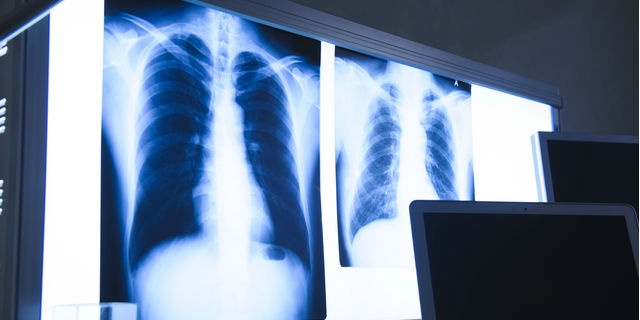

高齢者に多い誤嚥性肺炎…発症前に覚えておくべき予防対策リスト

「高齢者に多い誤嚥性肺炎…発症前に覚えておくべき予防対策リスト」のページです。デイリーニュースオンラインは、